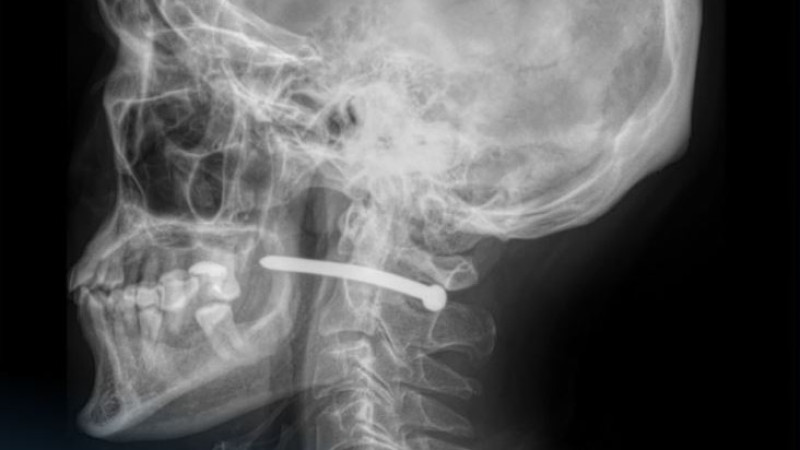

"Во время ремонта он по неосторожности получил травму гвоздём из пневматического пистолета. Рентгенография показала, что гвоздь прошёл очень близко к шейному отделу позвоночника", - отметили в медучреждении.

Врачи подчеркнули, что мужчине повезло, так как жизненно важные структуры не были повреждены.

"Травмы шейной области крайне опасны: рядом расположены крупные сосуды, нервы, дыхательные пути и спинной мозг. Даже небольшое повреждение может привести к серьезным последствиям", - добавили они.

Челюстно-лицевые хирурги больницы успешно удалили инородное тело, провели ревизию и обработку раны, а также наложили швы и стерильную повязку.